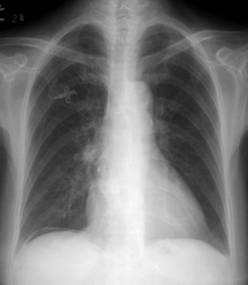

照片名称:正常胸片